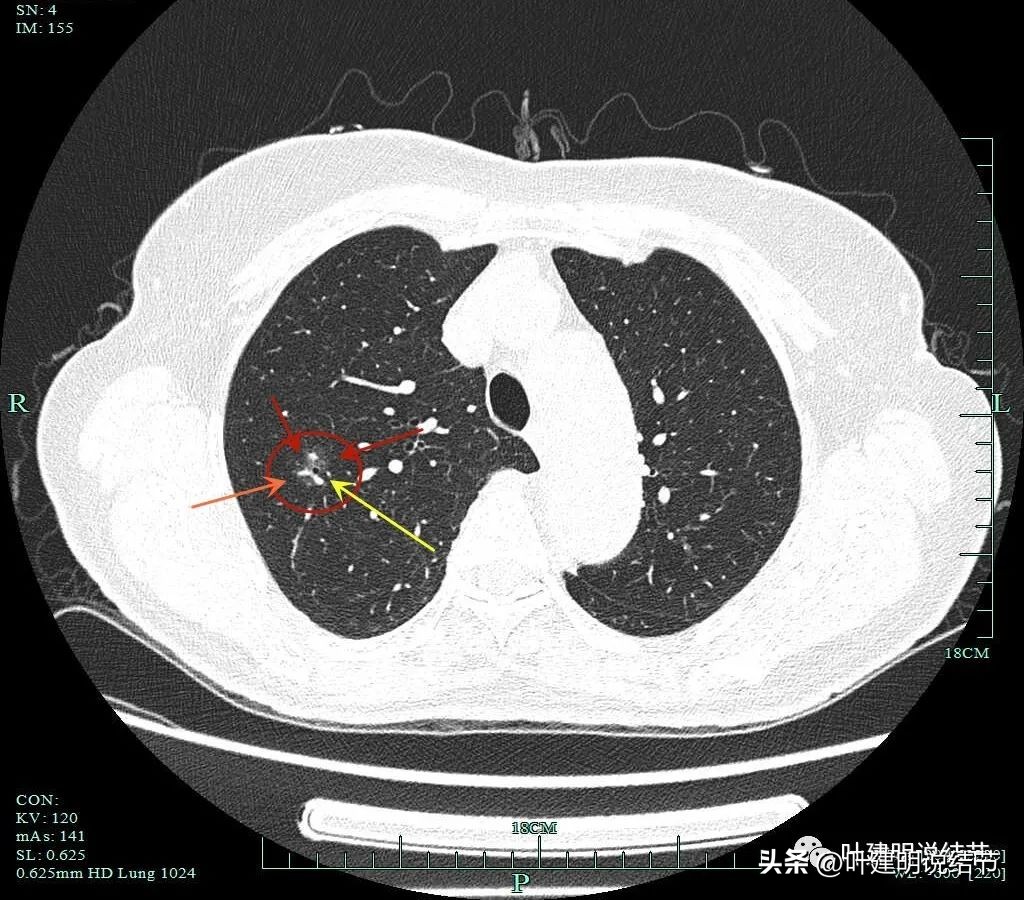

靶扫描重建发现病灶内部穿行血管毛糙,细支气管扩张,边缘毛刺样征。

灶内走行的血管模糊、异常增粗与毛糙。病灶总体轮廓较清,磨玻璃部分密度较低。

上图显示明显的血管弯征。而且磨玻璃病灶密度欠均匀。